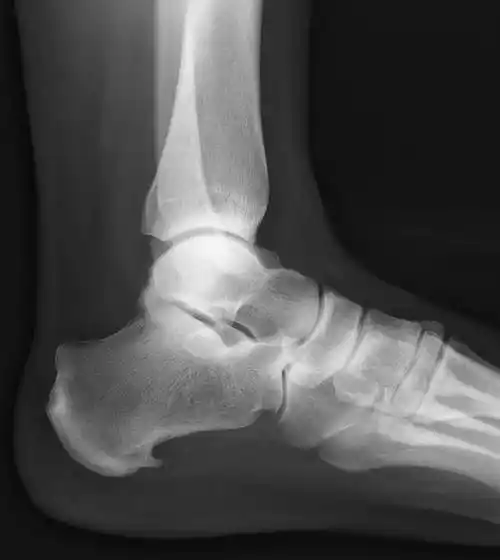

跟骨骨刺